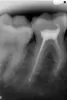

Ужасно болит зуб! При нажатии и сам по себе, ноет и пульсирует. Все это началось сразу же после того, как врач удалил мне нерв и запломбировал каналы. Я уже спать не могу, пью постоянно таблетки, а врач даже не сделал рентген! Сказал, если через неделю будет также, то зуб удалим! Я делала рентген сегодня сама в платной клинике! Стоматолог, делавший рентген, сказал, что, похоже на то, что в канале оставили инструмент. Посмотрите, это возможно?

Да, к сожалению, они правы. Там сломан инструмент и довольно глубоко. Поэтому достать его вряд ли удастся. Необходимо обойти инструмент, и на это способен только высококвалифицированный эндодонт. Зуб перелечить необходимо, иначе в ближайшее время вы его потеряете. Зуб рекомендую сохранить, это важно для вас.